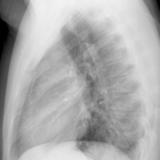

Case 8b Thymoma Lat

Date: 03/27/2009

Views: 14175